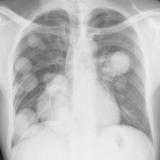

Nodules & Masses

Album: Nodules & Masses

Date: 01/25/2006

Size: 37 items

Views: 59832